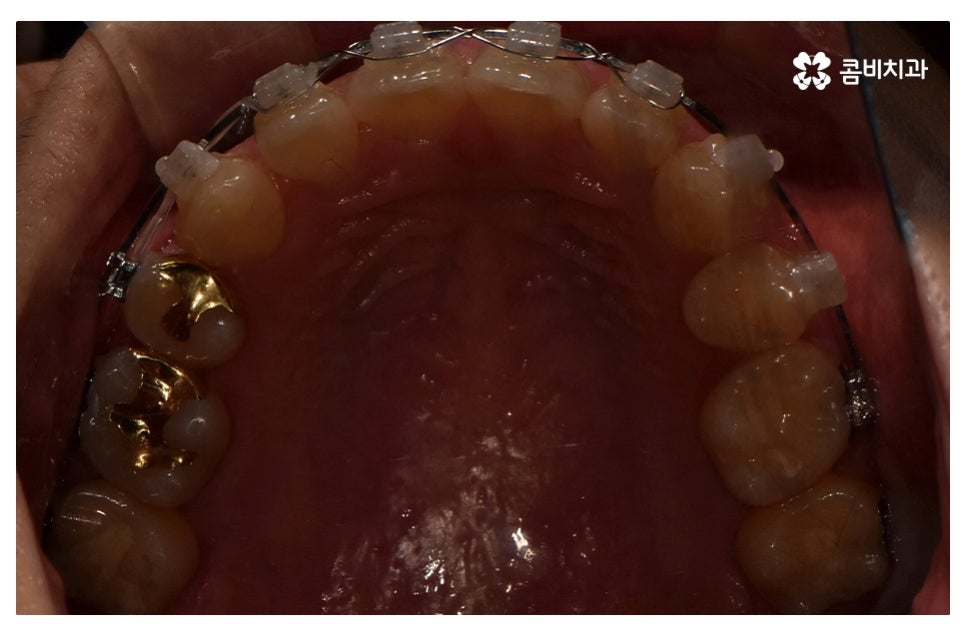

이번 포스팅에서 보인 덧니교정 사례의 경우 기능이 적은 작은 어금니를

발치하여 교정이 진행되었으며 발치를 진행하는 경우

작은 어금니를 발치하는데 충치 등으로 인해 손상이 큰 치아를

발치하는 경우가 일반적이라고 할 수 있어요.

물론 구강 내 치아의 이동 공간이 충분한 경우에는 비발치로도

덧니교정이 진행되는 경우도 있으며 덧니가 심하지 않은 경우에는

부분교정으로 치료가 진행되는 사례도 있어요.